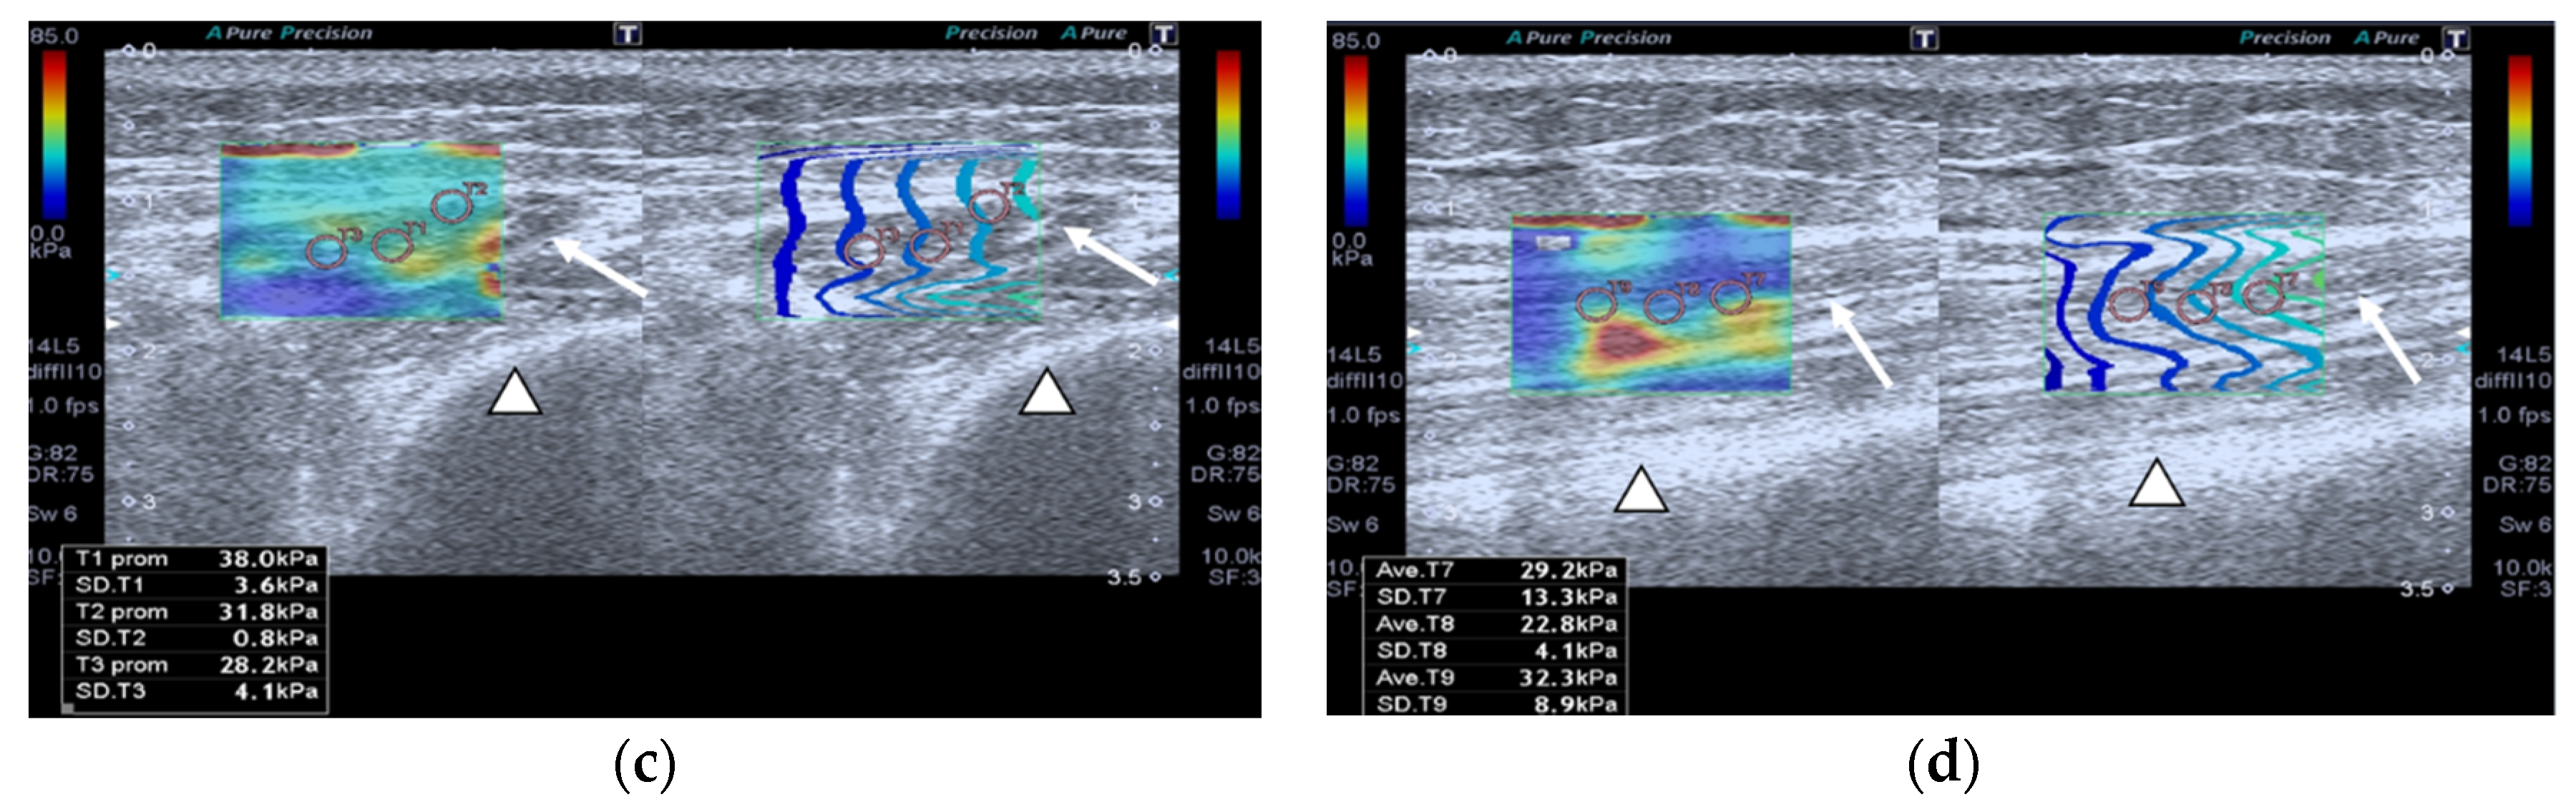

Both patients and healthy controls underwent a CEUS assessment of QRF muscle blood flow. An intravenous bolus injection of 4.8 mL of SF6 (sulfur hexafluoride) microbubbles (Sono-Vue®, Bracco, Italy), an intravascular contrast agent, was given via a cubital intravenous line. The microbubbles are recovered and stabilized by a phospholipid membrane. Additionally, this contrast is purely intravascular, meaning that the microbubbles will not go through the endothelium. Moreover, the size of the microbubbles is smaller than that of red blood cells. The contrast agent is eliminated from the body via expired air and has few side effects, which can include headache and abdominal pain. It can be used in patients that suffer from renal failure but cannot be used in patients with recent acute coronary syndrome or clinically unstable ischemic cardiac disease. CEUS can be measured quantitatively and qualitatively. In fact, the CEUS enhancement pattern (ROI) is a qualitative parameter and is shown in Figure 3a. Regarding the quantitative parameter, it is measured by a time–intensity curve that is obtained with our built-in software from Aplio 500 US device. After the infusion, the distribution of the contrast agent was visualized in the early arterial phase, which allowed us to assess the microvascular flow of the QRF muscle [12]. CEUS images were acquired, and time–intensity curve analysis of a CEUS video clip was then performed. After setting an ROI (pink circle) in the area of strongest enhancement, the following quantitative parameters were automatically calculated: peak intensity(×10−5 arbitrary units [AU]), which is the maximum intensity of the time–intensity curve; time to peak (seconds), the time needed to reach the peak intensity; mean transit time(seconds), the time when the intensity is higher than the mean value; slope(×10−5 AU/seconds), which is the maximum wash-in velocity of the contrast agent; and area under the curve(×10−5 AU · seconds), which is the integral value of the curve was associated with the total blood volume and the sum of the wash-in area and wash-out area.

Figure 3.

Transversal QRF muscle of a matched healthy control (85 years old). (a) Transversal ultrasonography scan shows the QRF muscle (arrow) and vascularization after contrast-enhanced ultrasound (CEUS) administration (arrowhead). CEUS image and time–intensity curve analysis are shown using the built-in software. (b) ROI (pink circle) in the area of strongest enhancement indicates maximum perfusion in the QRF. (c) ROI (pink circle) in the area of lowest enhancement indicates minimum perfusion in the QRF.

Images of the peak maximum and minimum CEUS intensity of a patient and a healthy control are shown in Figure 3 and Figure 4.